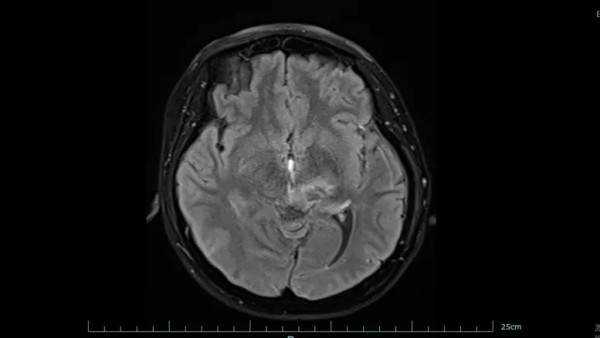

左为治疗前,右为治疗后。图片来源于稿源单位

好在经过系统治疗,黄女士的肿瘤明显缩小,病情得到有效控制。目前,她已回归正常生活和工作,生活质量显著改善。